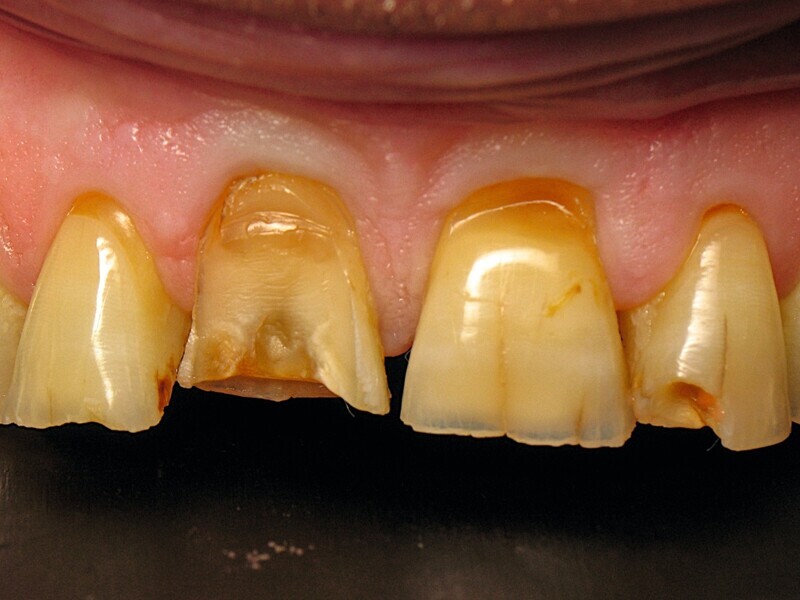

Une heure avant, la figure 10 montre un véritable patchwork de teinte dentaire. On constate une translucidité du bord libre, une saturation cervicale, des fêlures, des restaurations absentes, et une fracture coronaire complexe de la dent 11. Tous ces éléments ont amené les dents à réagir, en construisant au cours du temps, de la dentine réactionnelle a l’origine des nombreuses variations de teinte.

Dans le même temps, les figures 11 et 12 montrent la situation initiale de ce patient, venu en consultation pour la réhabilitation de ses incisives maxillaires. Le diagnostic a révélé un bruxisme nocturne à l’origine de plusieurs destructions coronaires : usure du bord libre, ab fraction, restaurations absentes, fêlures, et une fracture coronaire complexe. Il est aisé de comprendre pourquoi précédemment, le choix du matériau a été porte sur le zircone. Il est également facile de comprendre les motivations de ce patienta retrouver son sourire perdu. Cette dégradation par le temps est inéluctable, mais chez ce patient elle a été particulièrement rapide et agressive. Inverser le cours du temps est donc une évidence pour restaurer la santé dentaire de ce patient.

Fig. 11 : Situation initiale.

Fig. 12 : Vue rapprochée de la situation initiale